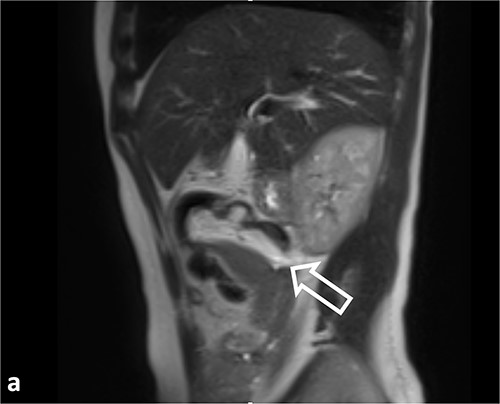

The radiologist’s description of the abdominal MRI with contrast has led to a suspicion of ‘intussusception’ in the transverse colon (Figs 2 and 3).

Coronal T2WI MR images. (a) Tubular lesion (thin arrow) consistent with hyperintense appendiceal mucocele is observed in the left upper quadrant of the abdomen. (b) Ileocolic intussusception is observed in the right lower quadrant of the abdomen (thick arrow).